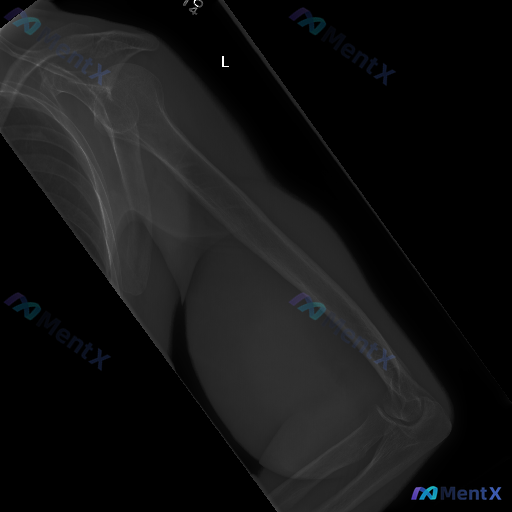

整理到一张左侧肱骨X光正位片的读片资料,影像科的客观描述如下: 1. 骨皮质连续性:肱骨干近、中、远端未见明确骨折线、皮质台阶感或成角畸形,连续性良好;骨小梁结构清晰,无压缩或不规则透亮区。 2. 关节对位:肩关节(肱骨头与肩胛盂)、肘关节(肱尺、肱桡关节)对位良好,关节间隙正常,无脱位/半脱位征象...